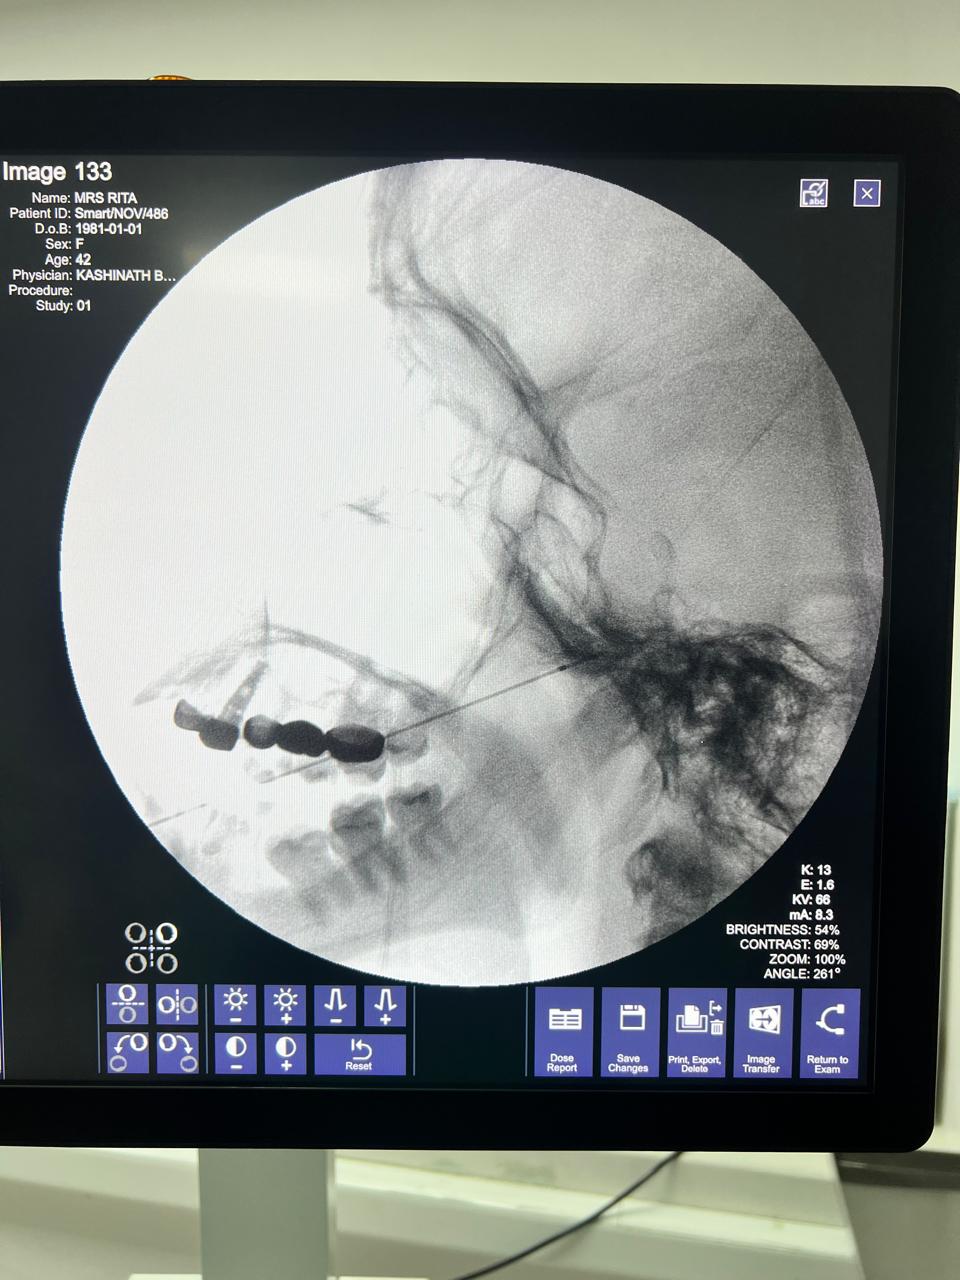

Think of radiofrequency ablation as a highly targeted intervention. Using real-time X-ray guidance (fluoroscopy), a specialized needle electrode is carefully positioned near the affected portion of the trigeminal nerve. Then, controlled radiofrequency energy is applied to interrupt those overactive pain signals.